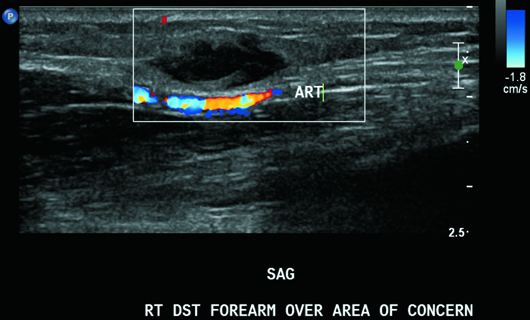

On targeted ultrasound, the palpable right volar forearm abnormality correlated with a 1.7 cm circumscribed but irregular, predominantly hypoechoic, subcutaneous focal mass without deeper extension into the muscle plane or vascular involvement (Figures 1, 2, and 3). The diagnosis of nodular fasciitis was confirmed histopathologically, based on the percutaneous biopsy specimen.

On ultrasound, nodular fasciitis typically presents as a well-defined isoechoic to hypoechoic mass with mildly increased vascular flow in the deep portion of the subcutaneous fat layer, adjacent to or in the fascia, as seen in this case.